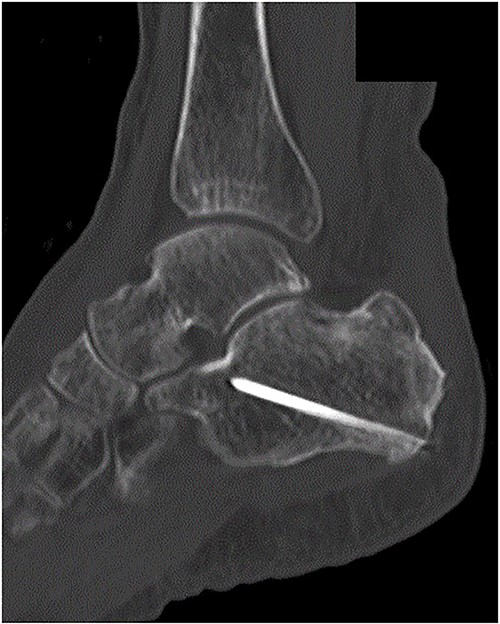

A 78-year-old woman complained of right heel pain when tripping during walking and visited to our hospital. She had medical histories such as arrhythmia, hypertension and hyperlipidemia. Physical examination revealed swelling, subcutaneous bleeding and tenderness on the posterior aspect of her heel and Thompson test was positive. Plain radiographs of the right ankle showed an avulsion fracture of the calcaneal tuberosity (Fig. 1). Non-contrast computed tomography (CT) demonstrated that the bone fragment was displaced. Based on medical histories, physical examination and image findings, we diagnosed an avulsion fracture of the calcaneal tuberosity and applied surgical treatment for the patient.

Plain radiographs of the right ankle showed no abnormal findings in (A) an anteroposterior view, but an avulsion fracture of the calcaneal tuberosity (B) a lateral view.